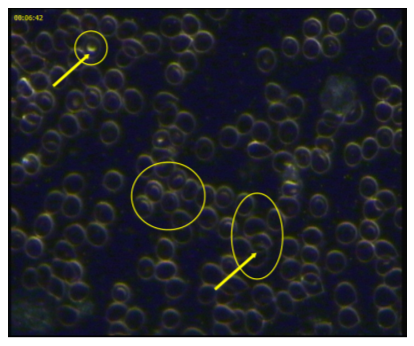

Before

Live blood analysis taken during July 2012 shows the red blood cells are clumped (erythrocyte aggregation) and do this when there is excessive inflammation. Excessive fat tissue is inflammatory. Lack of exercise and poor food choices also serve to increase inflammation throughout the body. Some red blood cells also have circles (amniocytes) present inside them indicating dehydration.

After

Live blood analysis taken during October 2012 shows the red blood cells are now floating freely. There are less inflammatory chemicals in the blood causing stickiness. Amniocytes are no longer present indicating diet and hydration has improved.